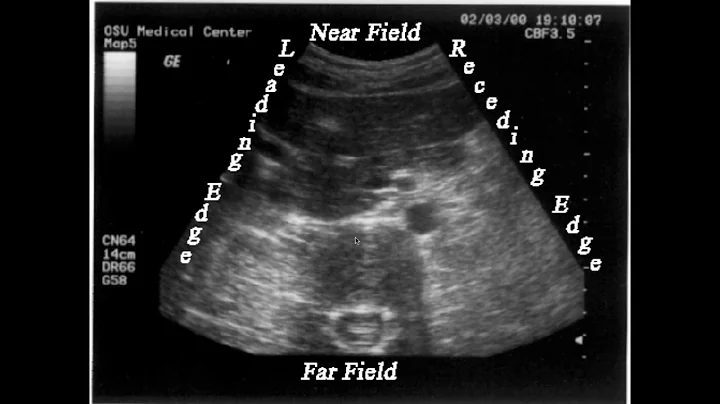

Ultrasonology: The Study Of Clinician-performed Ultrasound

In this webinar, David P. Bahner, MD, RDMS, distinguishes the difference between sound, ultrasound, sonography and ...